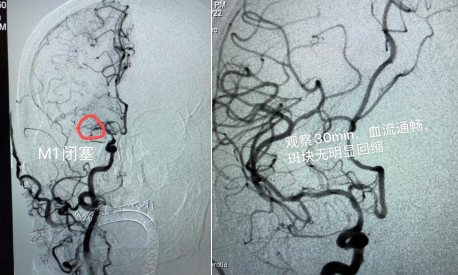

該患者男性,69歲,既往有高血壓、糖尿病、腦梗死等病史;主因“突發(fā)左側(cè)肢體活動(dòng)障礙5小時(shí)”入院;患者入院時(shí)神志嗜睡,煩躁不安,言語(yǔ)含糊,雙側(cè)眼球向右側(cè)凝視,雙側(cè)瞳孔等大、等圓,對(duì)光反射( + );左側(cè)中樞性面舌癱;左側(cè)肢體肌力0級(jí),右側(cè)肢體肌力5級(jí), NIHSS評(píng)分15分。入院后,立即啟動(dòng)卒中綠色通道,在頭顱CT排除腦出血后,進(jìn)行急診頭顱MRI+MRA檢查:右側(cè)顳葉梗死,右側(cè)大腦中動(dòng)脈閉塞。為進(jìn)一步明確病因,決定對(duì)患者實(shí)施腦血管造影+備支架機(jī)械取栓術(shù),盡最大努力挽救患者生命。時(shí)間就是生命!腦病科丁煜主任緊急與患者家屬溝通病情,取得了家屬的同意。在急診科、放射科、麻醉科、重癥監(jiān)護(hù)室、檢驗(yàn)科等多學(xué)科協(xié)作下,以腦病科邢錫熙主治醫(yī)師為首的神經(jīng)介入治療組迅速完成術(shù)前準(zhǔn)備,于入院內(nèi)1小時(shí)進(jìn)入導(dǎo)管室穿刺造影,發(fā)現(xiàn)患者右側(cè)大腦中動(dòng)脈M1遠(yuǎn)端閉塞,遂行支架機(jī)械取栓術(shù),一次性開(kāi)通血管;發(fā)現(xiàn)大腦中動(dòng)脈重度狹窄,在藥物維持血流無(wú)效的情況下,當(dāng)機(jī)立斷行球囊擴(kuò)張,血管順利3級(jí)開(kāi)通,觀察半小時(shí)血流通暢。

術(shù)前血管閉塞                  術(shù)后血管3級(jí)開(kāi)通

術(shù)后患者轉(zhuǎn)入重癥監(jiān)護(hù)室,術(shù)后6小時(shí)患者意識(shí)完全清醒,術(shù)后3天右側(cè)肢體肌力恢復(fù)至3級(jí),轉(zhuǎn)入普通病房,經(jīng)過(guò)半個(gè)月的精心治療,患者右側(cè)肢體肌力基本恢復(fù)正常,康復(fù)出院。